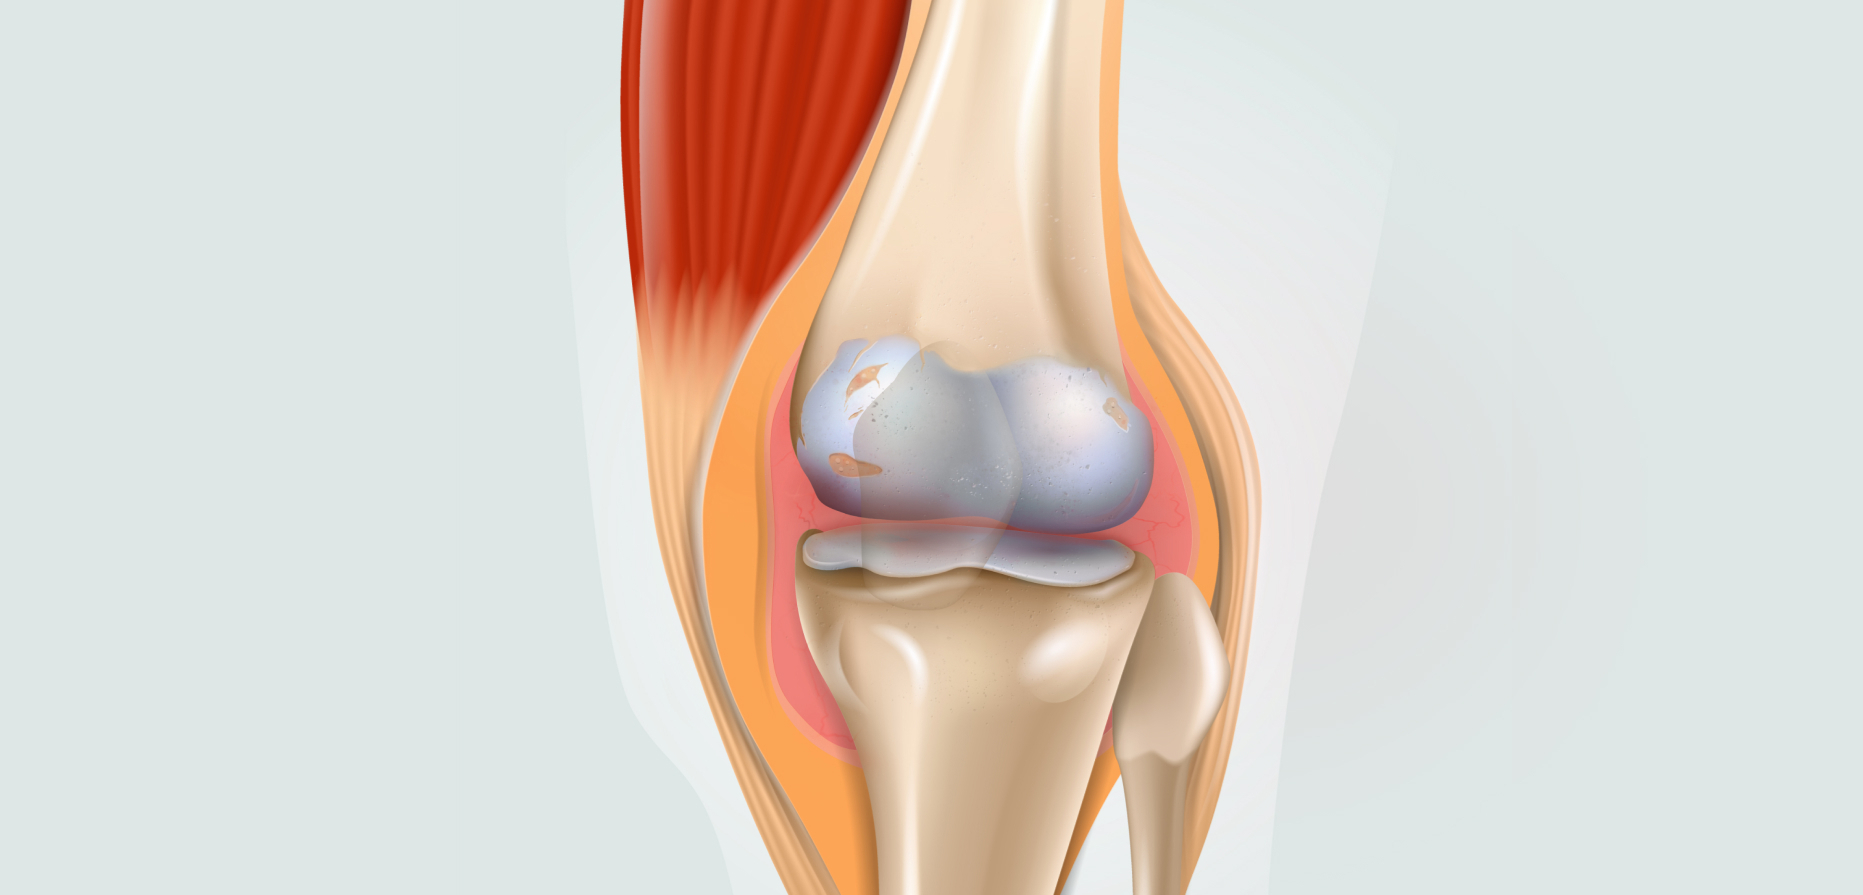

Суставная Жидкость и Головка Сустава: Обзор и Здоровье